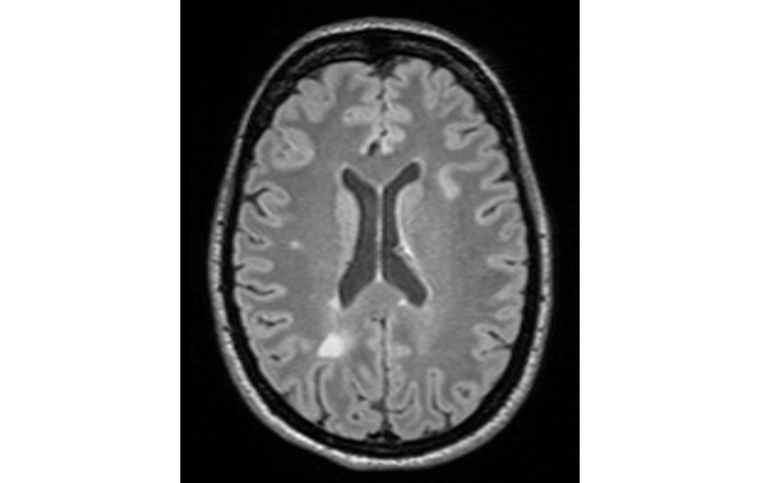

Für die Entwicklung der Plattform vereint das Konsortium die klinische, wissenschaftliche, technische und kommunikative Expertise von 15 öffentlichen und privaten Partnern aus neun verschiedenen Ländern – von Klinika über Universitäten zu kleinen und großen Unternehmen sowie einer Stiftung. In die Algorithmen einfließen sollen klinische Daten wie MRT-Bilder und Ergebnisse aus Blut- und Augenuntersuchungen, und zwar über den Verlauf der Krankheit hinweg. Zusätzlich sollen Patient*innen über eine App selbst Angaben zu ihren Symptomen, ihrem Befinden und auch finanziellen Belastungen beitragen können. Die Informationen werden pseudonymisiert und datenschutzkonform übermittelt, analysiert werden sie mit neuesten Deep-Learning-basierten KI-Modellen. Die Plattform soll dabei auch zusätzlich bestehende Krankheiten berücksichtigen können.